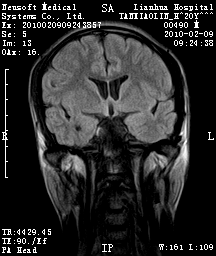

20岁男性患者,平时偶有头痛而无其他不适,现因持续头痛服药后无缓解而来院就诊。

松果体囊肿?

松果体区占位继发轻度脑积水?该患者有ct资料,我已发上。

考虑松果体囊肿。